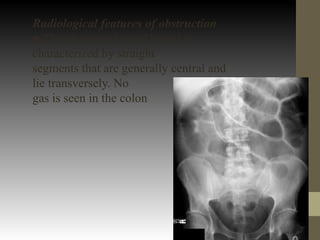

Radiological features of obstruction

■ The obstructed small bowel is

characterized by straight

segments that are generally central and

lie transversely. No

gas is seen in the colon